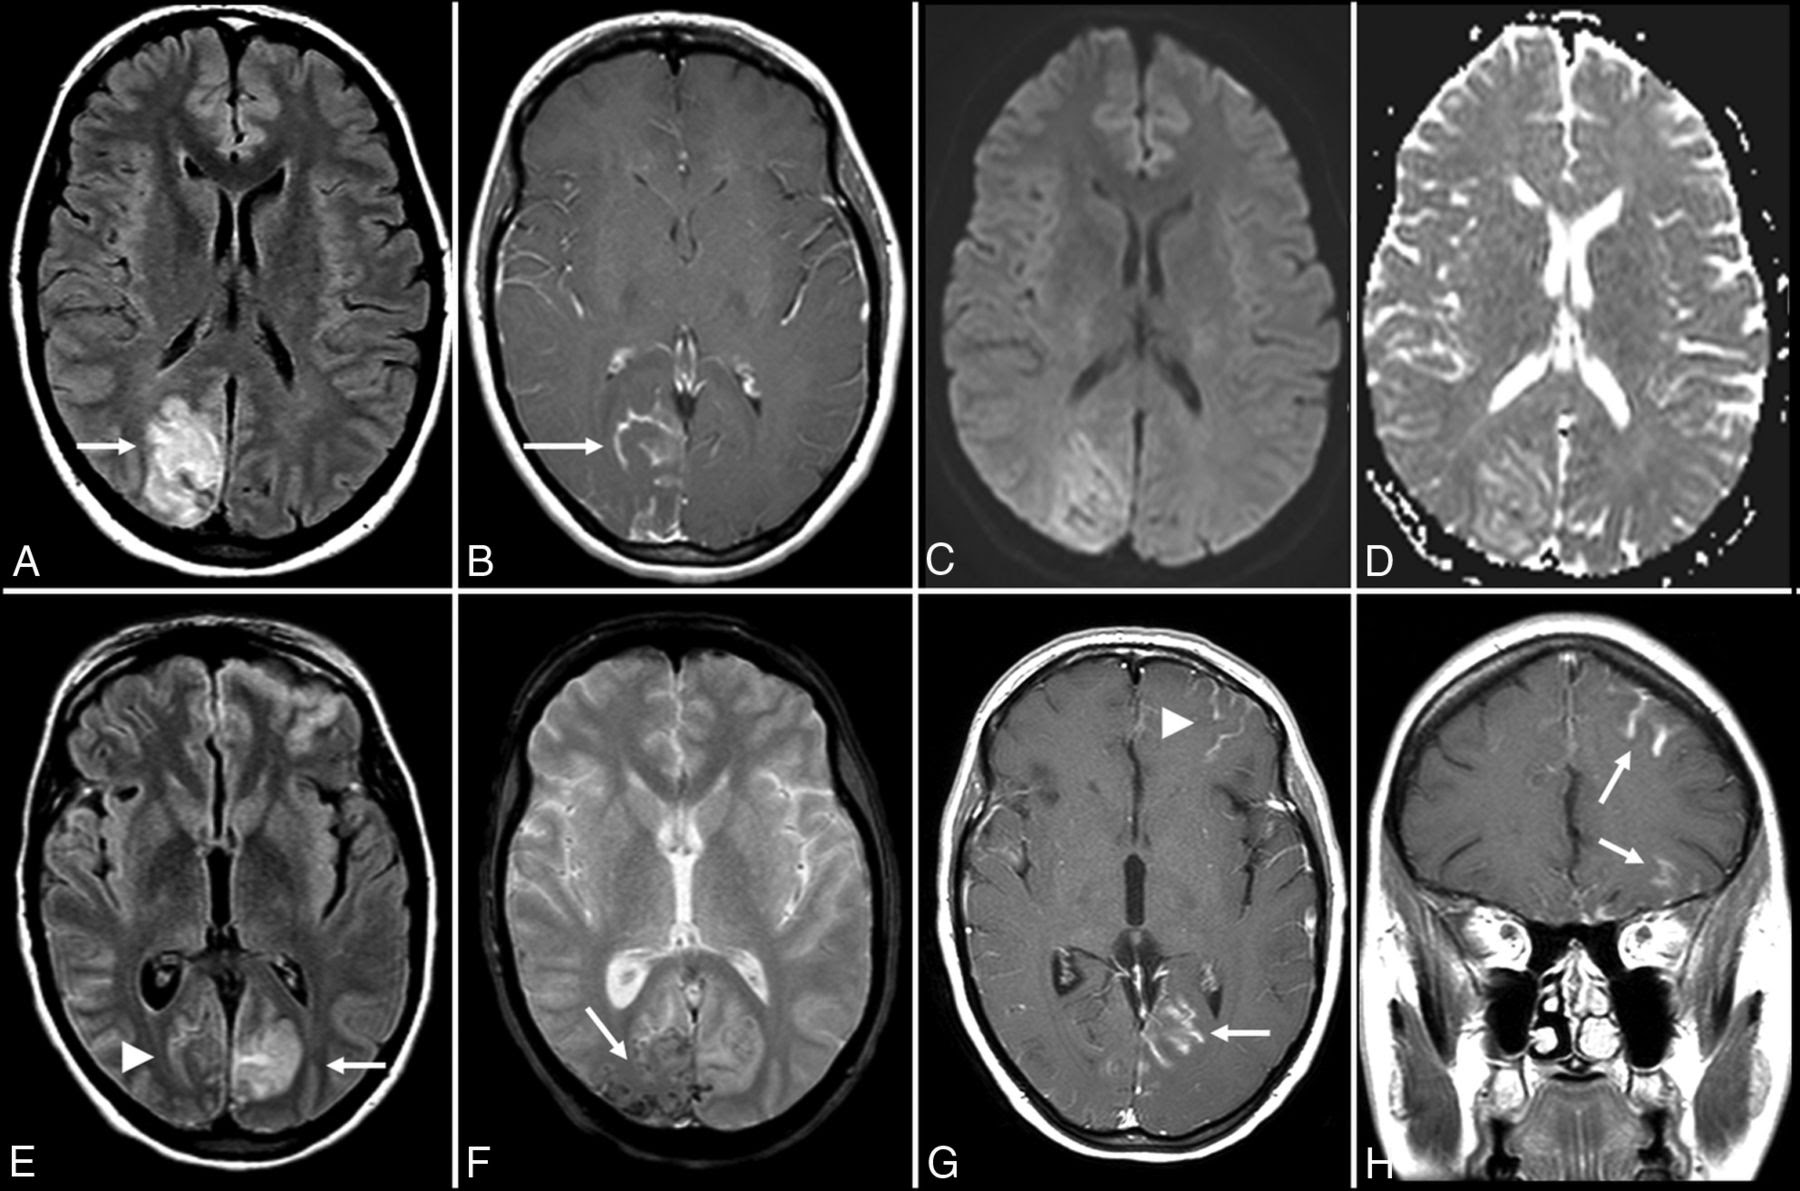

- MRI head: most sensitive and specific imaging modality [10]

- Findings

- Early stages : often no detectable abnormalities [12][13]

- Later stages: unilateral or bilateral hypodense zones in the temporal lobe

Always consider HSE when imaging suggests potential meningoencephalitis and temporal lobe involvement; bilateral temporal lobe abnormality is a pathognomic sign of HSE.

If encephalitis caused by herpes simplex virus is suspected, it is necessary to perform brain imaging methods (if possible, nuclear magnetic resonance, if not possible – computed tomography) and analysis of cerebrospinal fluid (in the absence of contraindications, such as the effect of plus tissue or coagulopathy).Research should be performed as an emergency. Nuclear magnetic resonance is a method of visualization of choice, violations are recorded in 90% of cases. Imaging of the brain helps to substantiate the diagnosis of herpetic encephalitis and to exclude contraindications for lumbar puncture. In this case, one-sided or asymmetric amplified signals are usually detected in the temporal lobes, the insular region of the cortex, and the orbital surface of the frontal lobes. These abnormalities are nonspecific for herpes. Differential diagnosis includes other causes of limbic encephalitis (such as paraneoplastic, autoimmune limbic encephalitis), cerebral gliomatosis (a rare brain tumor), middle cerebral artery ischemia, and status epilepticus consequences.